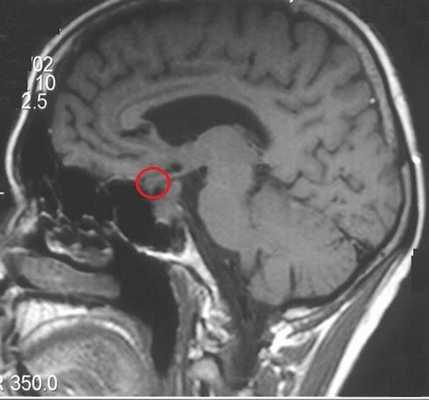

Микроаденома гипофиза (указана стрелкой) на снимке МРТ

Микроаденома гипофиза на снимках МРТ имеет ряд характерных признаков:

- неоднородная структура;

- округлая форма;

- очаг имеет гипоинтенсивный сигнал на Т1-взвешенных изображениях;

- выраженная граница, отделяющая образование от здоровых тканей;

- при наличии кровоизлияний и кист наблюдается усиление сигнала на Т2-взвешенных изображениях.